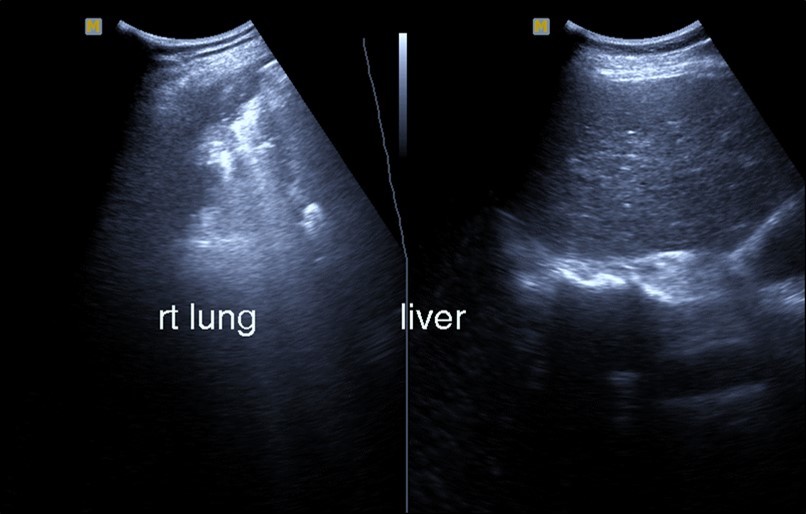

Figure 3.Chest ultrasound showing right lung segmental consolidation with positive air bronchogram.

Chest ultrasound showing right lung segmental consolidation with positive air bronchogram.

Bed side chest ultrasound may reveal positive findings as multiple Kerley’s B lines (>3 per intercostal space), pleural wall thickening (Figure 1), patchy areas of pulmonary consolidations especially in subpleural location (Figure 2, Figure 3) and obstructive lung collapse.